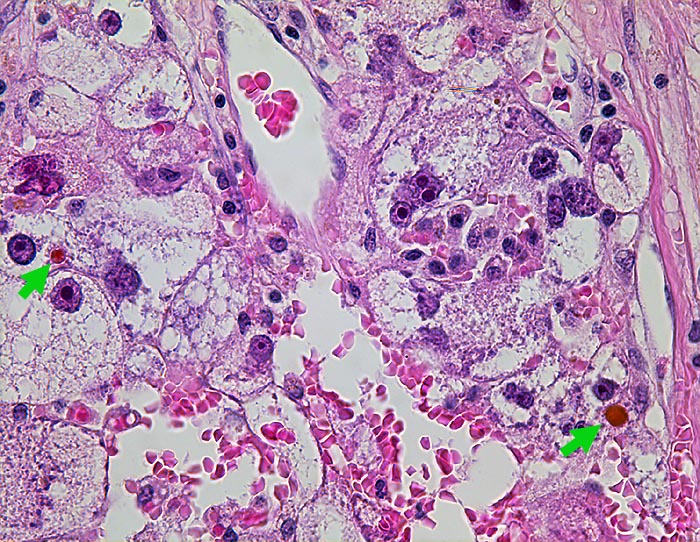

Hepatozelluläres Karzinom : Ovarmetastase

Tumorzellen mit reichlich vesikulärem Zytoplasma. Geringe Gallebildung.

Klarzellige und sarkomatoide Tumorareale.

St.n. Lebertransplantation wegen Hepatozellulärem Karzinom bei Hepatitis C vor 2 Jahren. Jetzt Metastasen von 12 und 14cm Durchmesser in beiden Ovarien.